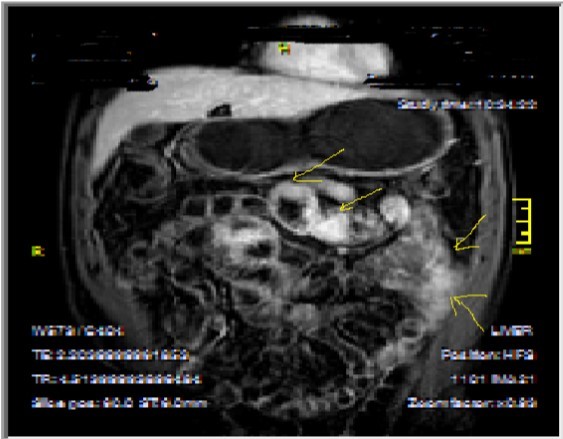

Chronic disease without active inflammation; Bowel wall thickening and enhancement on postgadolinium T1W images plus low signal intensity on T2W-FS images with possible stenosis and obstruction due to fibrosis, chronic disease with active inflammatoryexacerbations;these conditions can overlap with active inflammation, require longitudinal repeated scanning7, 12, 14, 20,26, 27, 28, 29, 30 (Figure 5a-b, Figure 6a-b)

Figure 6b.Heterogeneous bowel wall and mucosa involvement with collaborating skip lesions, specific for Crohn’s disease, predominant in ileum and terminal ileum which are shown at T2W coronal sequence after OCA, regarded at 39 years old female with severe disease.